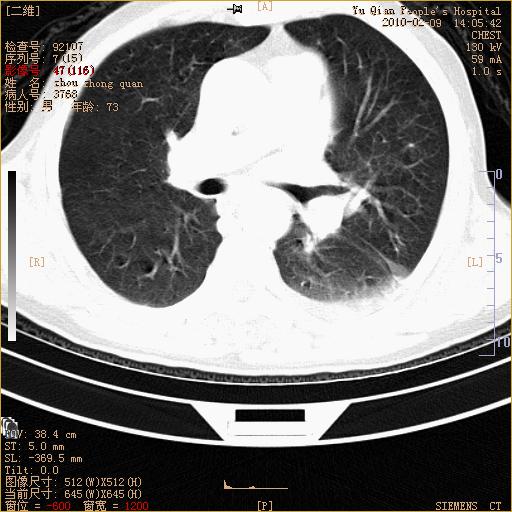

男性,73岁,咳嗽咳血数天,诊为肺ca伴左肺下叶后段阻塞性炎症、肺不张妥否?

右下肺有转移?

左下肺中央型肺癌伴结段形肺不张,左侧胸腔积液,纵隔内见部分增大淋巴结(反应性增生或转移)

左下基底干支气管明显变窄。

左肺下叶基底段支气管狭窄,左肺门增大,左肺下叶团片状病灶。中心型肺癌伴柱塞性炎症可能大,建议支气管镜检查。

左下肺中央型肺癌伴节段性肺不张,左侧胸腔积液,纵隔内见肿大淋巴结

左下基底段支气管变窄。建议进一步纤支镜检查。

1、左肺下叶后基地段肺癌伴阻塞性炎症,左下肺门淋巴结转移。2、左侧胸腔积液。